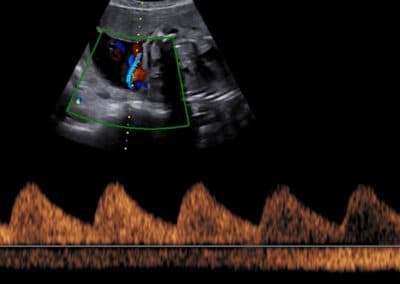

Dopplerovské vyšetření uterinních arterií v 11.-14. týdnu těhotenství

Měření PI (index pulsatility) v uterinních arteriích dle FMF protokolu

Protokol pro správné měření PI (index pulsatility) v uterinních arteriích:

CRL 45-84 mm (11-13+6 týden) Sagitální řez dělohou se zobrazením kanálu děložního hrdla a jeho vnitřní branky, následně mírné sklopení sondy a aplikace Dopplerovského barevného mapování za účelem identifikace uterinních arterií Měření PI (index pulsatility) v oblasti vnitřní branky Gate 2mm Odklon průběhu uterinních arterií 0-30º od vertikální osy Měření PI (index pulsatility) ze třech bezprostředně následujících podobných pulsních vln Kalkulace průměrného PI (index pulsatility) obou uterinních arterií

Ukázka správného snímku zobrazujícího Dopplerovské vyšetření uterinních arterií.